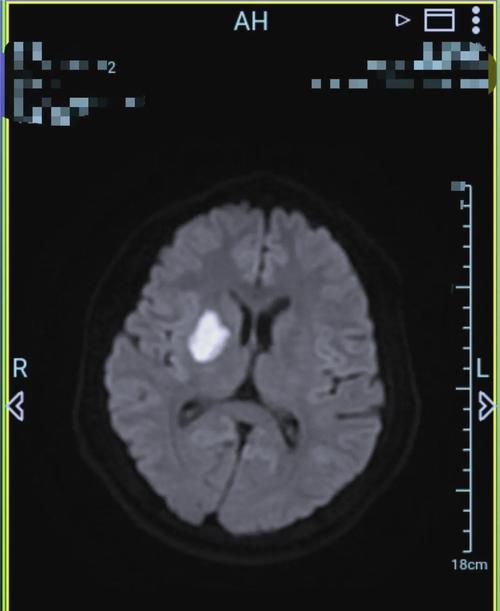

卢脑右侧基底节区腔梗

(图片来源网络,侵删)